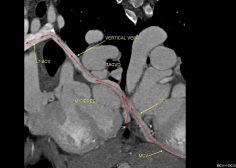

Atretic coronary venous sinus ostium ( CS) , Total Anomalous Coronary Venous Drainage to LT BCV (TACVD).

The middle & great cardiac veins (MCV & GCV) drain into a left sided vertical vein ( same course of persistent LSVC) to left BCV & also a vein draining the anterior wall of the RV ending into the left vertical vein . U must notify the surgeon this item so as not to ligate this thought persistent LSVC / vertical vein to any reason as in partial cavo-pulmonary connection (Glenn shunt) otherwise catastrophic sequale will happen.

so in any congenital CT study make sure the CS ostium is patent & not atretic.